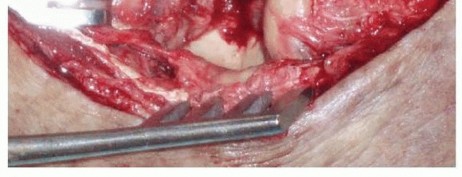

The lateral approach is the workhorse for the treatment of terrible triad injuries, providing access to the LCL complex, the radial head, and, in many cases, the coronoid. A direct lateral incision is made, typically utilizing the Kocher interval between the anconeus and the extensor carpi ulnaris (ECU). However, the astute surgeon will often abandon formal anatomic intervals and instead utilize the traumatic dissection that occurred at the time of injury. In most cases, the LCL and common extensor origin have been avulsed from the lateral epicondyle, creating a massive traumatic window directly into the joint. If an anteromedial facet fracture is present, a separate medial incision is utilized. The medial approach involves identifying and protecting the ulnar nerve, followed by splitting the flexor carpi ulnaris (FCU) or utilizing an "over-the-top" approach anterior to the medial epicondyle to gain orthogonal access to the coronoid.

Step 1: Fix the Coronoid Fracture. The coronoid is addressed first, often through the lateral traumatic window after the fractured radial head fragments have been temporarily excised or retracted. Small transverse tip fractures (Type I) are often capsular avulsions and can be secured using heavy nonabsorbable sutures passed through the anterior capsule and tied over the dorsal aspect of the proximal ulna via drill holes (the "capsular lasso" technique). Larger fragments (Type II) can be fixed with retrograde cannulated screws from the dorsal ulna. Anteromedial facet fractures demand a medial approach and rigid fixation with a mini-fragment buttress plate to resist varus shear forces.